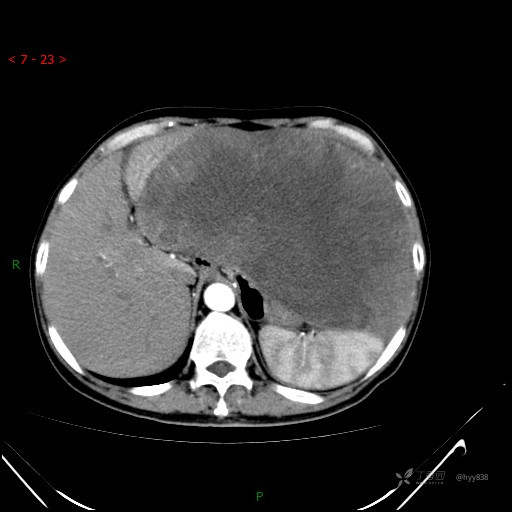

增强动脉期